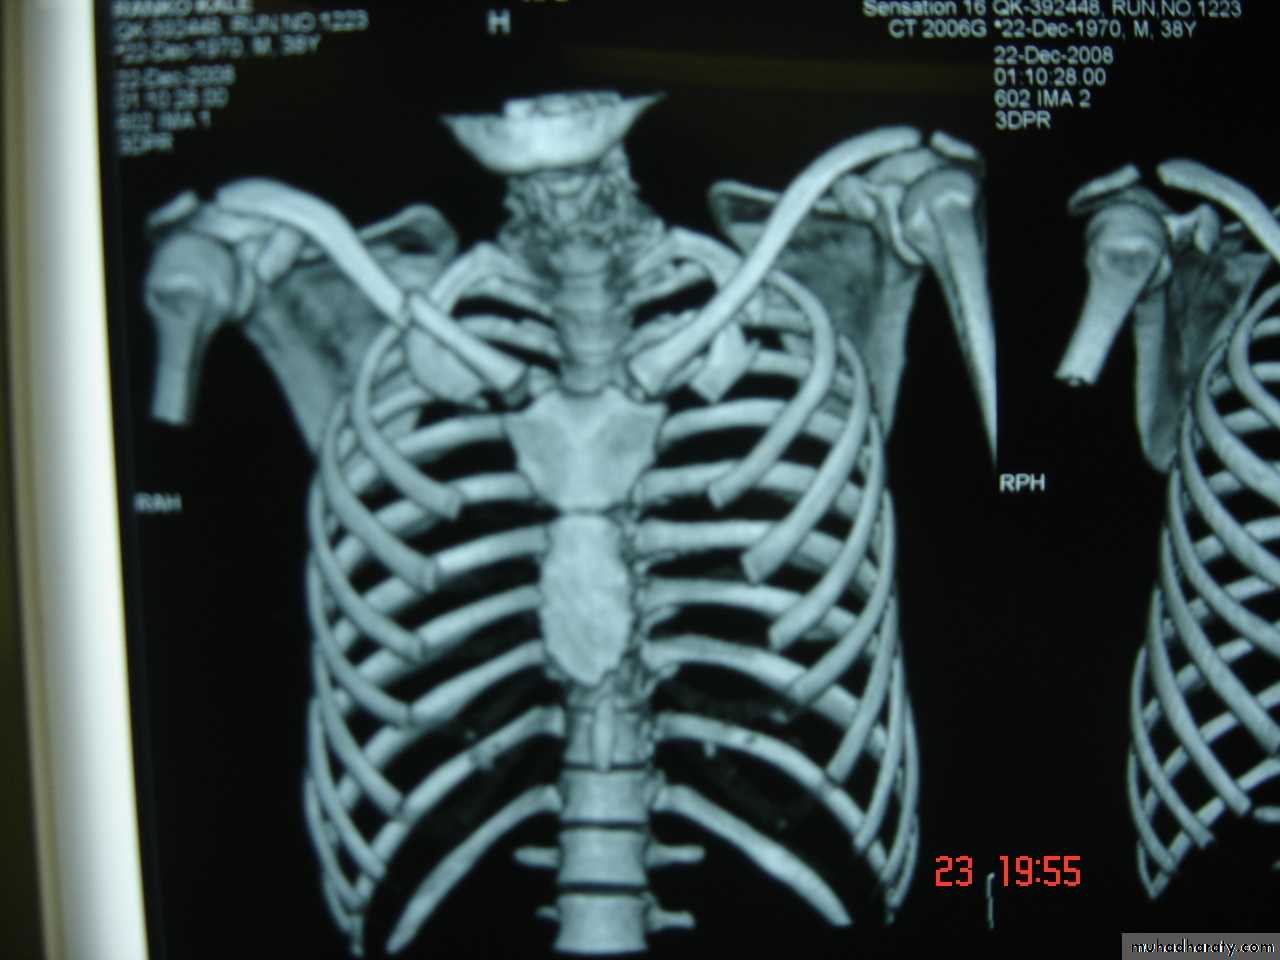

2-Ribs & Sternal injuries May lead to Single rib fracture the important thing is to relief pain by . analgesic , chest wall strapping or intercostal nerve block or Multiple ribs fractures , flail chest in that case four or more ribs are fractured anteriorly and posteriorly which lead to paradoxical respiratory movement with the resultant hypoxia and severe dyspnea that nictitates emergency intubation and assisted ventilation and if the patient needs prolonged intubation for more than one week then tracheostomy is indicated .

Fractures